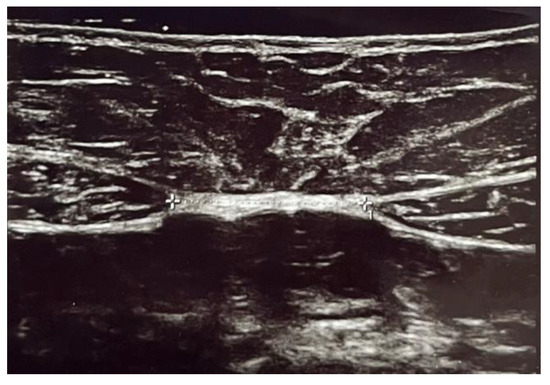

| DRA superior | 2.12 ± 0.98 | 2.1 ± 0.77 | 0.94 |

| DRA inferior | 0.98 ± 0.9 | 1.33 ± 0.87 | 0.009 |